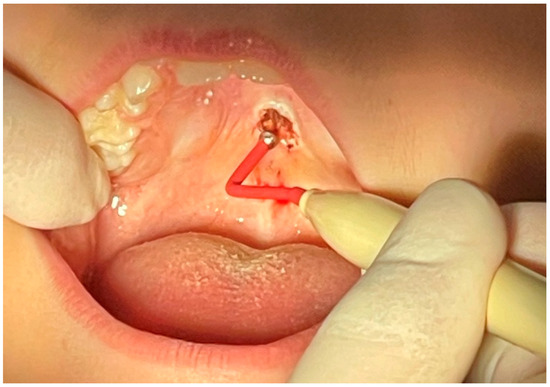

Intraoral Lipoma on the Palate of an 11-Year-Old Patient: A Case Report

2. Case Presentation